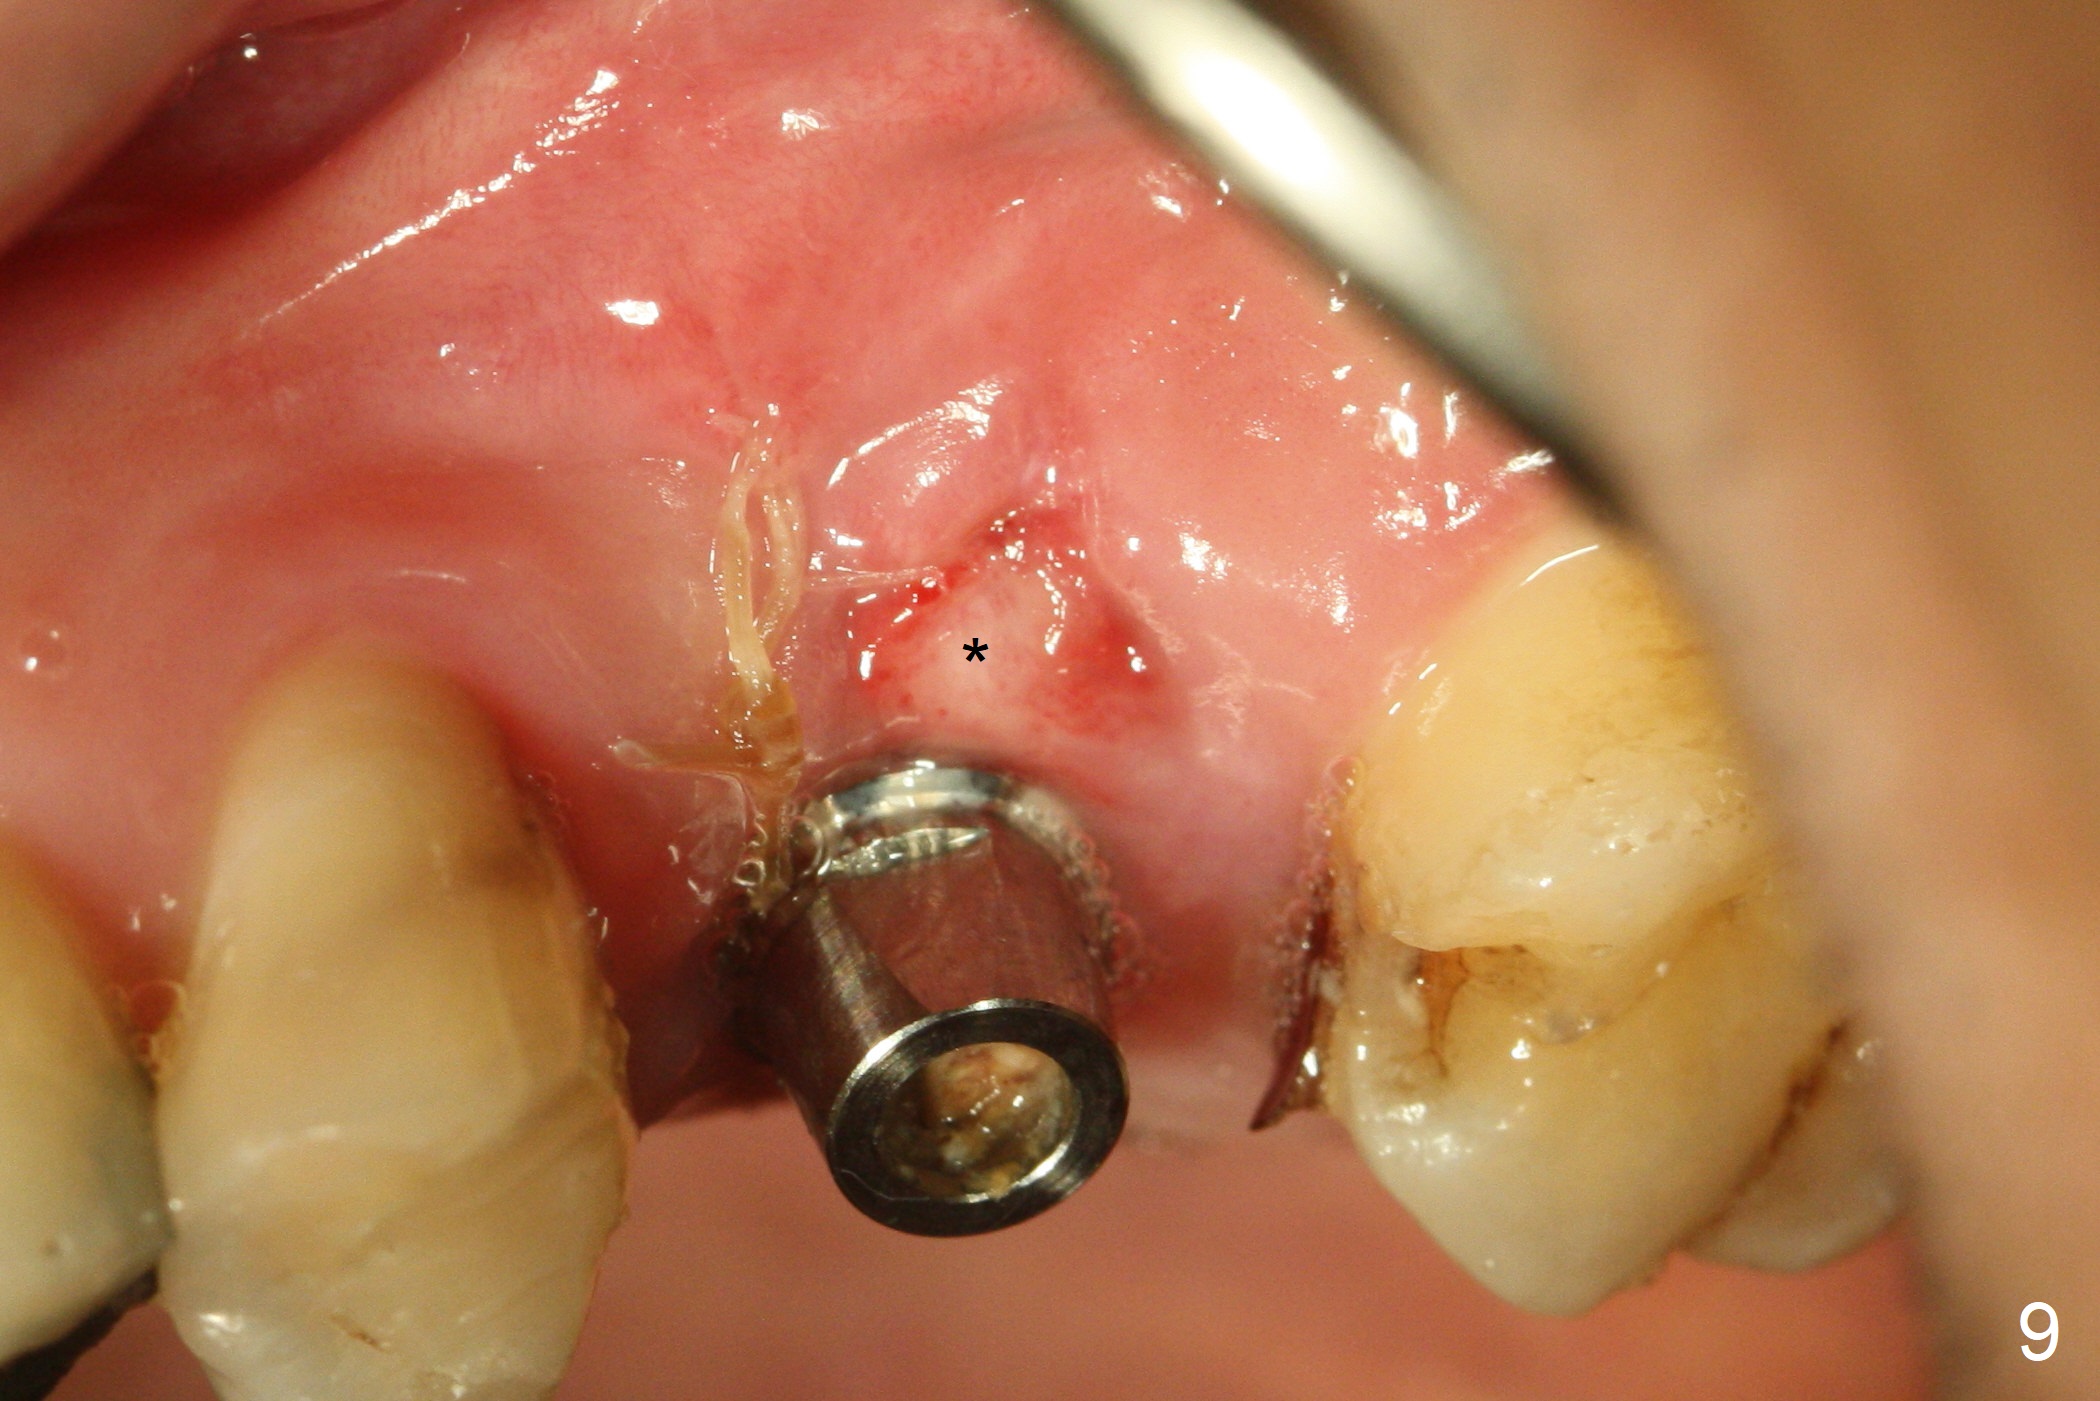

After extraction of the distobuccal residual root of the tooth #14 (Fig.1 arrow), the gingiva around the socket does not look like the keratinized one (Fig.2 *). An osteotomy through the distobuccal socket would seem too buccal for immediate implant. The palatal gingiva feels too tough to be stretched. An incision is made (Fig.3 dashed line); with elevation, the thick flap is transferred buccally (curved arrow). An osteotomy is initiated in the palatal bone with 1.5 mm drill, followed by Magic Expanders until 4.3 mm for 11 mm (Fig.4,5). Following Magic Drill 3.8x13 mm, the sinus membrane is found to be perforated. The latter is repaired with Osteogen plug. A 4.5x9 mm IBS implant is placed with 50 Ncm (Fig.6). Osteogen plug and allograft (Fig.7 *) are inserted into the remaining distobuccal socket (reduced after bone expansion). When a 5.5x4(4) mm abutment is placed, the transferred flap appears to be adapted to the distobuccal defect (Fig.8 *). Later one suture is placed for fixation. After provisional insertion, periodontal dressing is applied. Nine days postop, the periodontal dressing dislodges. When the loose provisional is removed for recementation, the flap seem to have healed (Fig.9 *). The gingiva heals around the abutment 5 months postop (Fig.9); the distal socket appears to heal while the bone graft remains at the crest (Fig.11,12). When #30 develops buccal abscess, the patient masticates on the left, leading to loss of composite at #13 (Fig.14); in fact the abutment at #14 is incompletely seated.